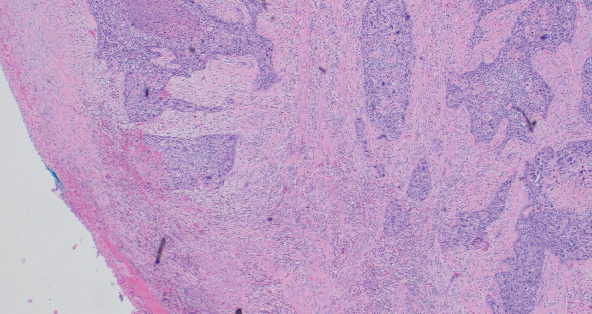

原发性子宫内膜鳞状细胞癌(PESCC)是一种罕见的病理。有关诊断和治疗的数据有限,完全基于病例报告和系列。我们报告一个独特的情况下,绝经后妇女的历史,艾滋病毒和肛门癌s/p放射治疗8年前。患者的首发诊断是有恶臭的阴道分泌物,抗生素难治性。尽管进行了广泛的检查,但患者自出现症状以来诊断明显延迟,但最终通过妇科肿瘤手术分期诊断为IB期PESCC。尽管她有肛门癌病史,并接受过不完整的盆腔放疗,但在肿瘤委员会上讨论了该病例,并认为该患者可以接受外束放疗。在我们的报告中,我们详细讨论了患者的表现、病程和治疗,并回顾了文献。

Primary endometrial squamous cell carcinoma (PESCC) is a rare pathology. Data regarding diagnosis and treatment is limited and is solely based on case reports and series. We report a unique case of a postmenopausal woman with a history of HIV and anal cancer s/p radiation therapy 8 years prior. The patient's presenting diagnosis was malodorous vaginal discharge refractory to antibiotics. The patient had a significant delay in diagnosis since the onset of symptoms despite extensive workup but eventually underwent surgical staging by gynecologic oncology with a diagnosis of Stage IB PESCC. Despite her reported history of anal cancer for which she received an incomplete course of pelvic radiation, the case was discussed at tumor board and the patient was deemed a candidate for external beam radiation therapy. In our report, we discuss, in detail, the patient's presentation, course, and treatment and review the literature.